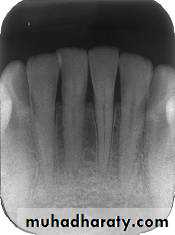

Mandibular incisor region

Mandibular canine region

Mandibular premolar region

Mandibular molar region